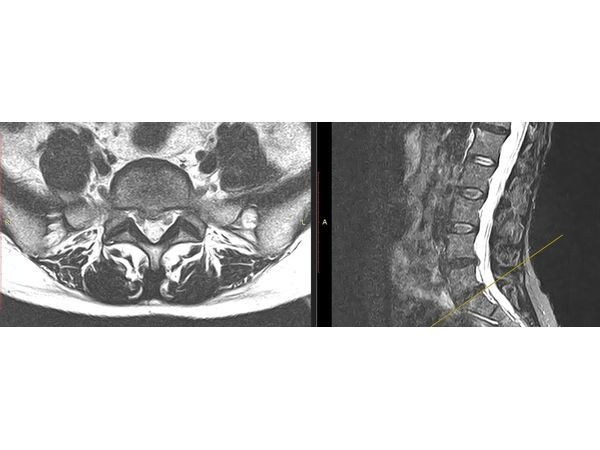

По результатам МРТ:

- две медианно-парамедианные экструзии — смещение дисков L4–L5 и L5–S1 к центру и вбок до 3,5 мм без вовлечения дурального мешка, окружающего спинной мозг;

- артроз фасеточных суставов в этих сегментах I–II степени — начальная стадия разрушения в местах сочленения суставных отростков.